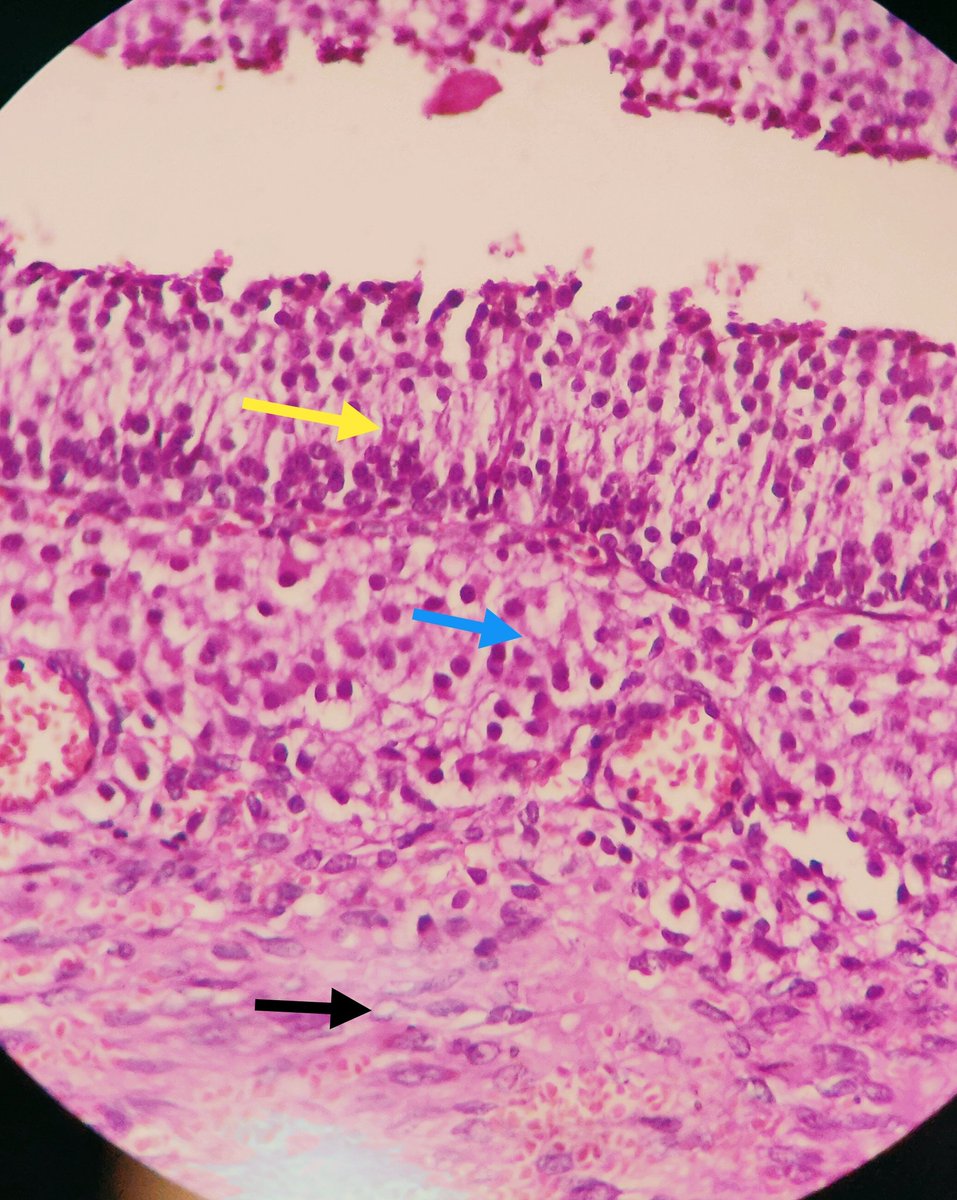

For the PGY1s in Pathology.. #gynpath #histology #PGY1 #OVARY #normalhistology Image1- mature graffian follicle Image2- Yellow: Granulosa layer Blue: Theca interna Black: Theca externa

Image1- mature graffian follicle

Image2- Yellow: Granulosa layer

Blue: Theca interna

Black: Theca externa